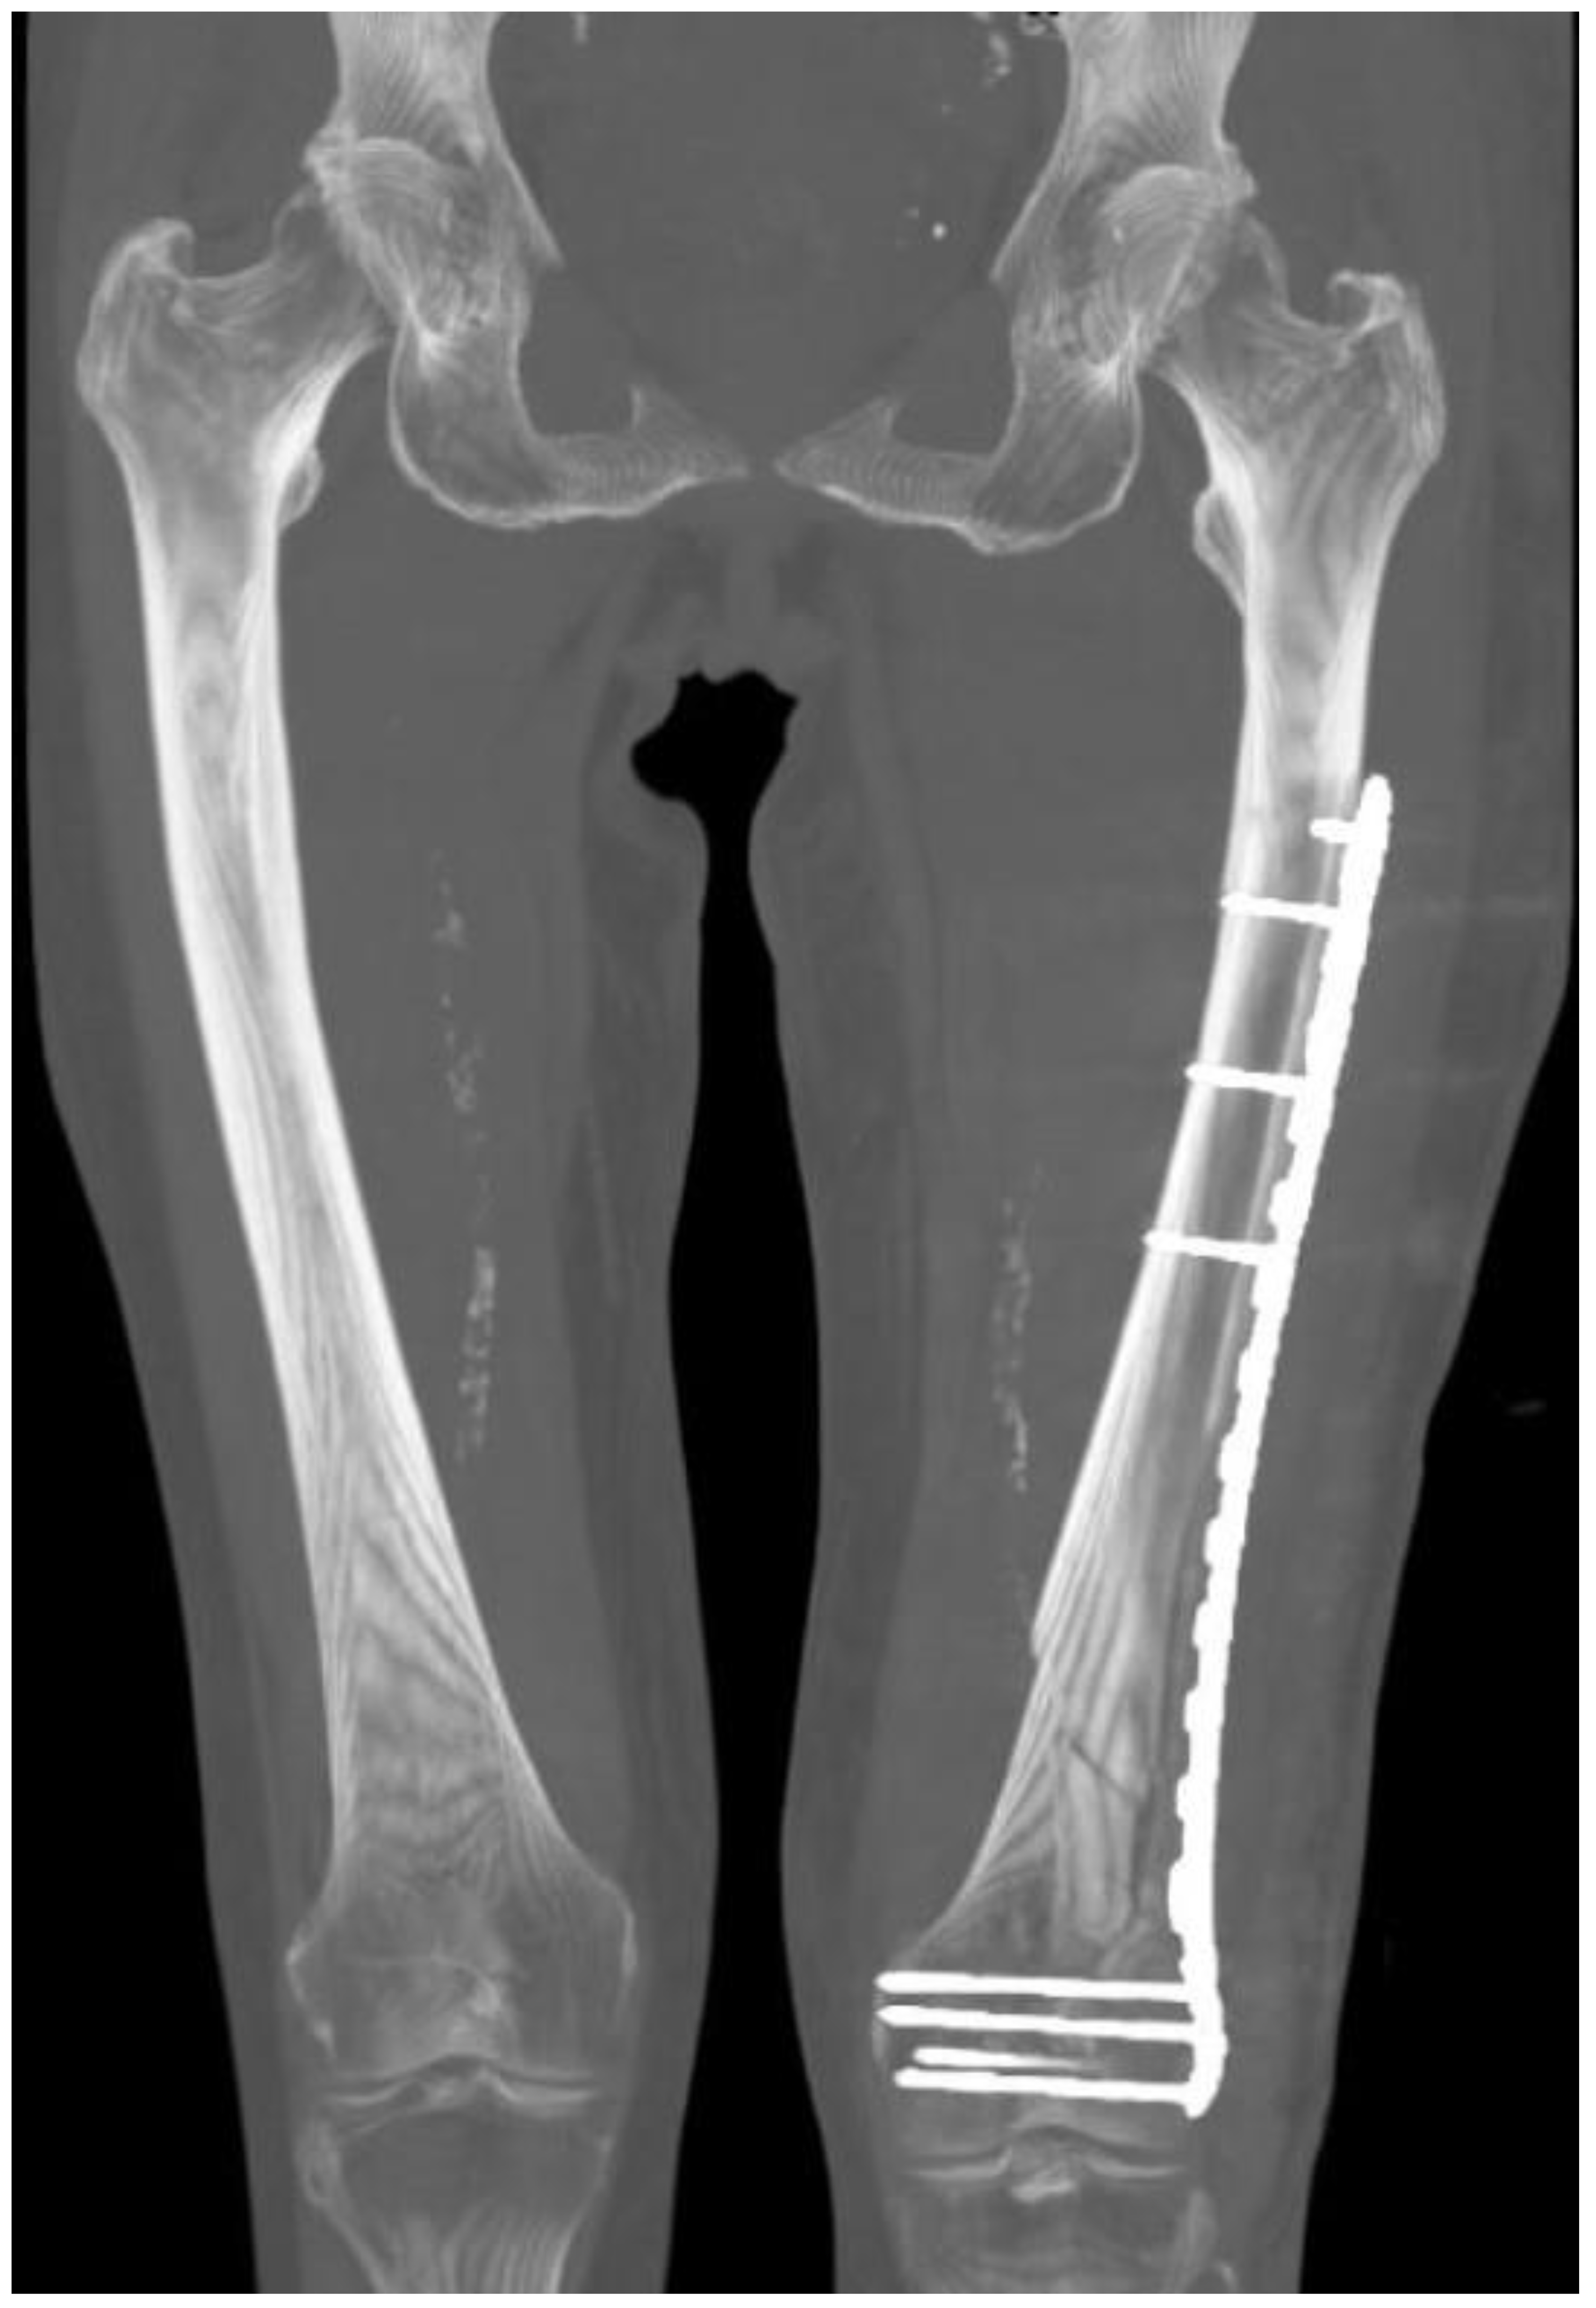

Internal Fixation for Fractures OrthoInfo AAOS How Does Traction Work For Fractures Traction on a fracture table for delayed intramedullary nailing, make sure it is placed far anterior, off the coronal midline to avoid. Traction is a set of mechanisms for straightening broken bones or relieving pressure on the spine [ 1 ] and skeletal system. Force is exerted directly on the bone by tongs inserted into the skull or a pin. How Does Traction Work For Fractures.